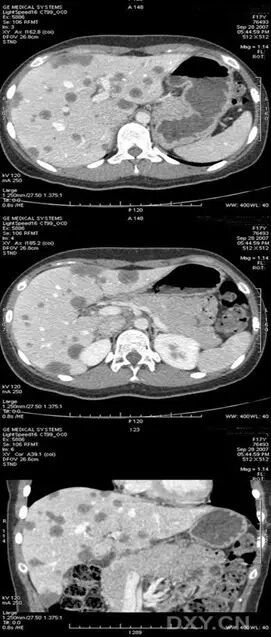

女性,17 岁。反复右侧腹部疼痛,再发伴加剧 1 周。素健,无疫区、疫水接触史。生化全套无异常。影像:CT 肝内多发大小不等类圆形低密度影,边界清楚,内密度上均匀;

MR 平扫 T1 加权像呈低信号,T2 加权像呈高信号及稍高信号影,增强后病灶可见环形强化,部分可见少量造影剂进入。诊断:肝上皮样血管内皮瘤;本病是一种少见的血管源性肿瘤,多发生在软组织以及肺、骨、脑、及小肠等脏器,原发于肝脏者非常少见。

本病是一种属于中度或低度恶性肿瘤,恶性程度介于肝血管瘤与肝细胞癌、肝血管肉瘤之间,生长缓慢,转移率低,总体发生率为 27%-45%,其中最常见的是转移到肺部,预后相对较好,肿瘤多位于肝脏的周边区域,肝脏包膜无膨隆。

CT 平扫为低密度影,病灶中心更低密度,约 20% 病灶可有钙化,增强后动脉期主要表现为周边强化为主,延迟后肿瘤实质内造影剂进入,而中央低密度区无强化。MRI 显示肿瘤 T1W1 呈低信号,T2W1 呈高信号,伴低信号晕圈。而凝固坏死、散在出血区呈低信号。肝动脉造影显示肿瘤血管丰富,肝包膜下病灶可呈「碗状」着色。

3.2 肝晕征是肝癌 CT 征象之一,晕征与肝癌的包膜有关, 包膜由肉芽组织和许多小血管组成, 包膜内血流较肿瘤内血流缓慢, 因此, 在动脉早期,瘤体明显增强,而包膜尚未强化, 在动脉晚期, 瘤体密度降低,而包膜继续保持高密度,这是肝癌特征性征象之一。